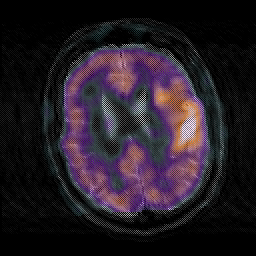

Subacute Stroke, overlay -- Slice #17

[Home][Help][Clinical] Slice 17